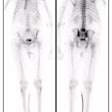

Acute renal failure is characterized by relative preservation of renal blood flow and extraction of tubular agents with a rising renogram curve (Retained cortical activity at 20 minutes (RCA) will be almost 100%). Extraction of glomerular agents in acute renal failure is low. The kidneys are usually of normal size.

In chronic renal failure there is severely and proportionately reduced renal blood flow and tracer extraction of both tubular and glomerular agents. The kidneys are often small in size. The renogram curve is typically flat with a low count plateau. In end-stage renal failure the kidneys are only faintly discernible from blood pool activity.